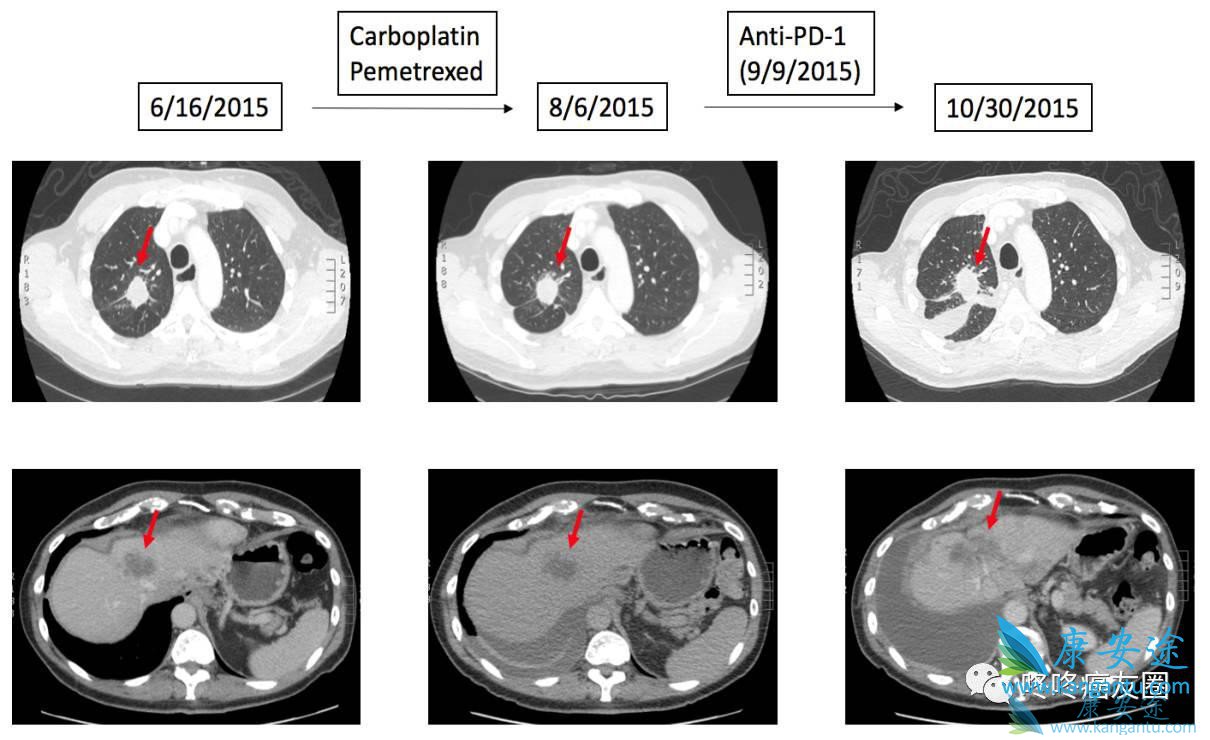

54岁,肺腺癌,基因检测显示患者具有EGFR E746-A750del 和T790M突变,经过化疗和EGFR 抑制剂治疗之后耐药,改用PD-1抗体Opdivo治疗。用药1.1个月之后,患者的状态变差,呼吸困难,CT显示,患者的肿瘤增大125%。

73岁,肺腺癌,基因检测显示患者具有EGFR L858R和T790M突变,经过化疗和EGFR 抑制剂治疗之后耐药,接下来使用PD-1抗体Opdivo治疗。1.7个月之后,CT显示患者的肺部病灶稳定,但是肝部病灶增大53.6%,同时还有肝部新发病灶。